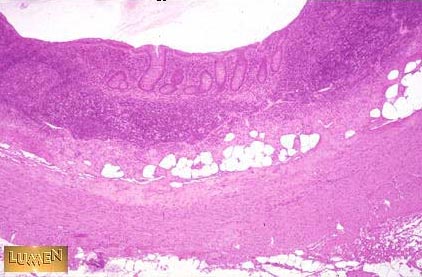

Is the outer layer of this organ serosa or adventitia?

Answer

Serosa - the Appendix is a peritoneal organ